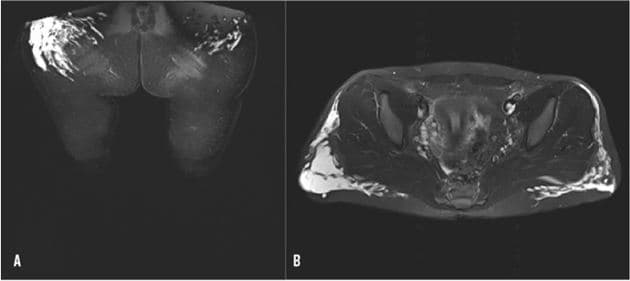

MR-skanningsbilleder af glutealområdet med væskeforandringer i begge baller (A) og på bagsiden af begge lår (B).

En 24-årig, tidligere rask kvinde blev henvist på mistanke om sarkom pga. en øm bule på venstre lår. Ved den objektive undersøgelse fandt man flere tumorer på venstre lår, og efterhånden udviklede patienten påvirket gangfunktion og morfikakrævende smerter. Læs mere om diagnosen og forløbet i kasuistikken af Uth og Mallet:

Hygromdannelse efter liposuktion og -grafting i glutealområdet